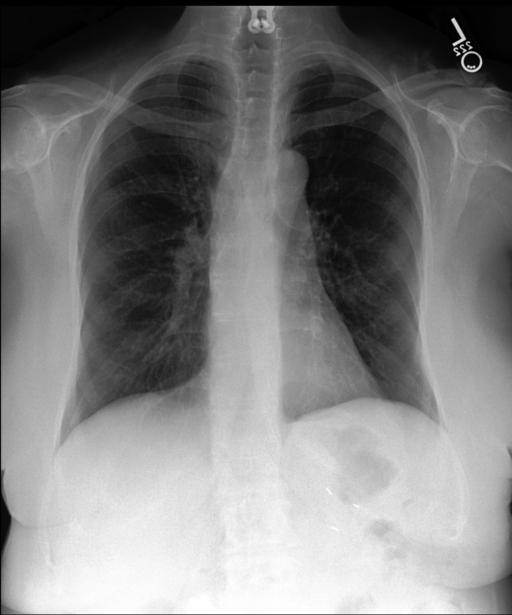

Probs: 0.229, 0.913, 0.941, 0.881, 0.896, 0.525, 0.058, 0.094

Report:

The lungs are clear.

No focal consolidation.

No effusion.

No pneumothorax.

The cardiomediastinal silhouette is normal.

No displaced rib fractures are noted.

There is no evidence of a compression deformity…

The thoracic spine demonstrates mild degenerative changes.